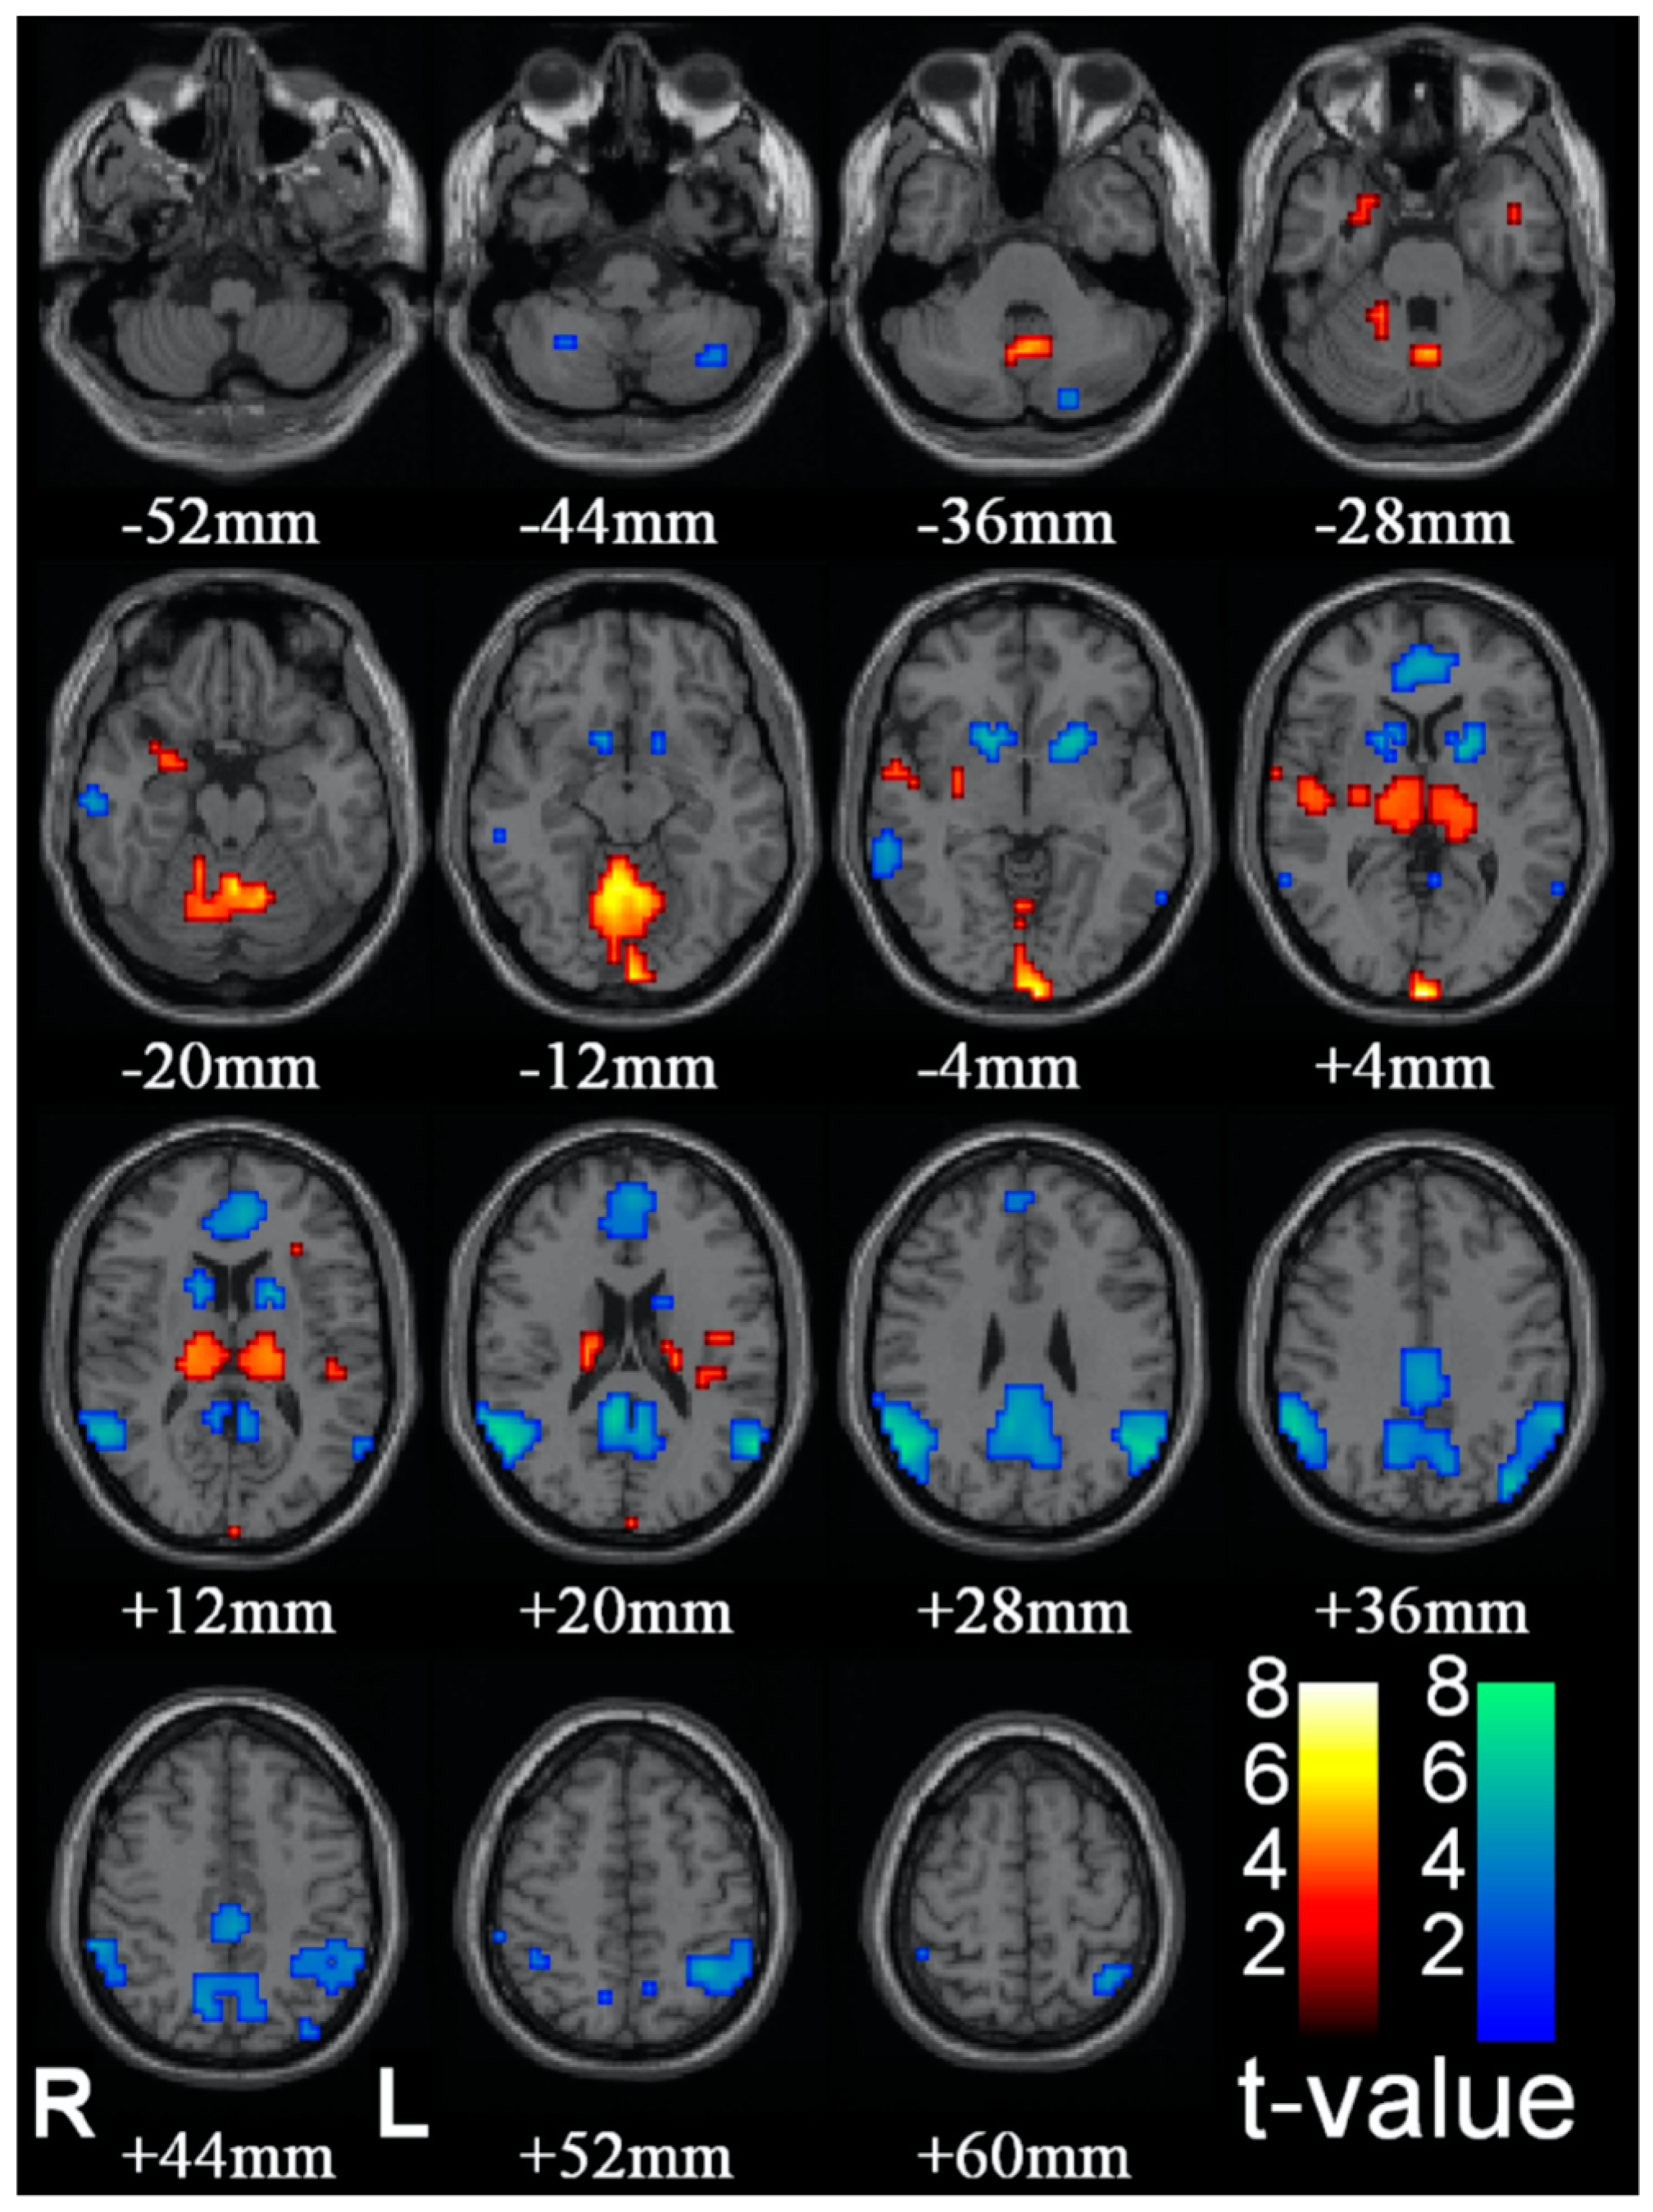

Blumenfeld [40], see [41], develops a proposal for the substrate of C* based on clinical indices of observable disruptions in the state of C*, such as epileptic absence (petit-mal) seizures. Group data of the effect of such seizures are reproduced in Figure 4. The logic of the analysis is that absence seizures represent a reportable and behaviorally corroborated loss or steep reduction of C*, though they are not accompanied by the loss of muscle tone associated with sleep. The subject will remain in an upright seated posture, for example, but stop speaking for the few seconds which comprise the duration of the seizure, and exhibit confusion on returning to C*. Thus, brain regions showing a decrease in activation during this period should be associated with the normal C* that is disrupted during this period, while those showing increases may best be interpreted as being inhibitory centers.

The brain regions showing consistent reductions in fMRI activation during petit mal absences are the ventral striatum in the region of the nucleus accumbens and the caudate nucleus (blue patches from −4 to +12 mm in Figure 4) and medial and lateral components of the DMN (blue patches from +4 to +60 mm in Figure 4). Remarkably, some brain regions show marked increases in fMRI activation during the absences, notably the thalamus (orange patches from +4 to +12 mm in Figure 4) and what appear to be some medial structures in the cerebellum (orange patches from −20 to −12 mm in Figure 4). These are probably best interpreted as inhibitory brain loci, with the thalamic inhibition emanating from the reticular nucleus of the thalamus, which is an inhibitory net surrounding the thalamus that acts as a gating mechanism to control sensory input to and from the cortex.

Figure 4. Changes in brain activity during epileptic absence seizures (from [40]).